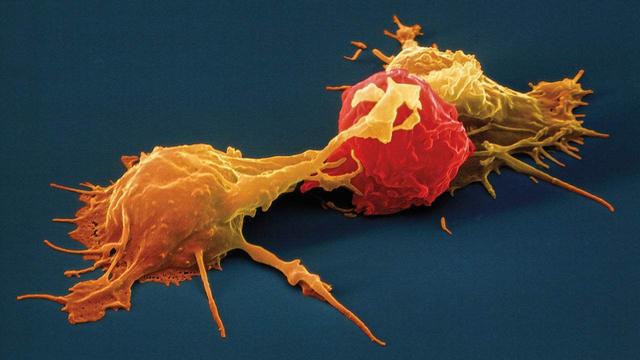

想象一下,你的肺,那可是你呼吸的发动机啊,突然间被这些看不见的小家伙给占领了,你的身体就成了它们的战场。那种感觉,就像是有人在你的胸口上压了一块大石头,让你喘不过气来。这种肺炎,可不是随便吃点药就能好的,它需要我们全力以赴,才能把那些讨厌的家伙赶出去。

但是,别怕,我们不是孤军奋战。医生们都是我们的战友,他们有各种武器——抗生素、药物,还有先进的医疗设备,都在帮我们对抗这些顽固的敌人。